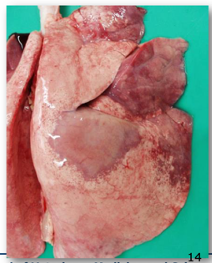

Pasteurella pnuemonia/septicaemia in a lamb

This a fibrinous pneumonia.

* Affected parts: usually the cranioventral lung regions. They feel consolidated/hard and not spongy.